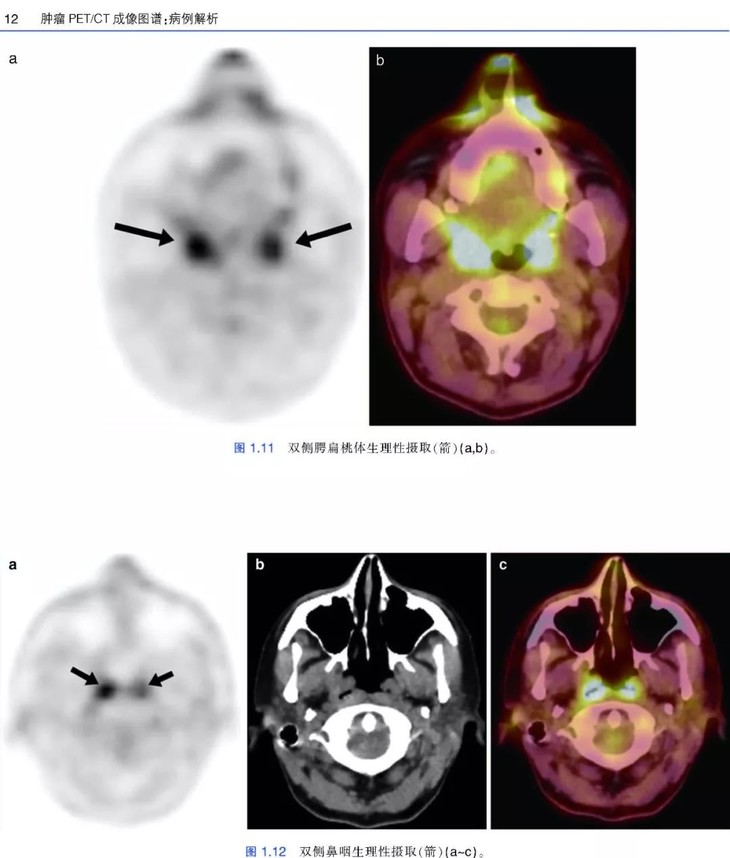

《肿瘤PET/CT成像图谱:病例解析》PET/CT扫描仪的出现,意味着功能代谢信息和解剖数据的融合,开创了医学领域的新纪元,特别是肿瘤学领域。自从PET/CT出现于研究中心,就成为肿瘤影像学中不可或缺的工具。《肿瘤PET/CT成像图谱:病例解析》涵盖了很多关于恶性肿瘤18F-FDG PET/CT诊断和治疗的临床病例。全书共两部分内容,第1部分为FDG PET/CT基础知识,包括18F-FDG的生理分布、正常变异、良性病变和技术伪影。第2部分涵盖了大量临床肿瘤病例,包括常见和罕见表现。每个病例都按照简要病史、影像表现描述、影像表现解释的顺序进行论述,最后是由相关文献支持的学习要点。本书中的所有病例均经组织病理学证实。本书适合核医学、放射学、肿瘤学、肿瘤放射学和核医学技术专业的住院医师和执业医师阅读。

• 涵盖全身各部位肿瘤的临床病例和大量PET/CT图像;

• 图片清晰,内容描述简明扼要,便于读者阅读和理解;